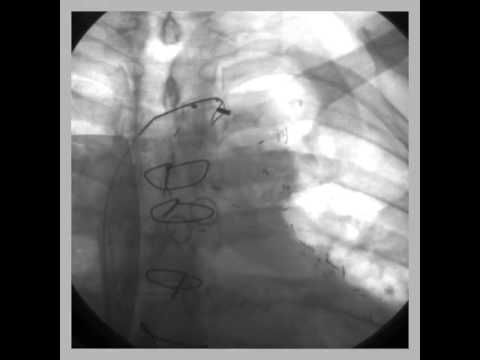

Video 60.1 Initial AP cine demonstrating three bipolar leads in typical locations. Note that the leads appear to move as one unit through the left brachiocephalic vein, where there is lead-to-lead binding.

Video 60.2